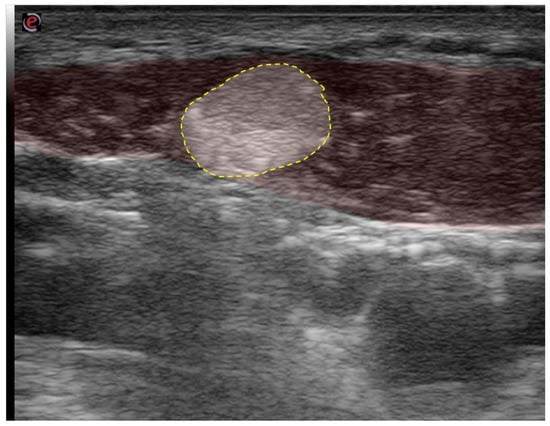

| Obliquus capitis inferior (OCI) | Ipsiversion of head | +++ | +++ | SSPcap, RCM, vertebral artery, greater occipital nerve | Adjacent muscles are all extensors of the head |

| Rectus capitis major (RCM) | Extension of head | +++ | +++ | SSPcap, OCI | |

6.2. “Expect the Unexpected”—Variant Anatomy